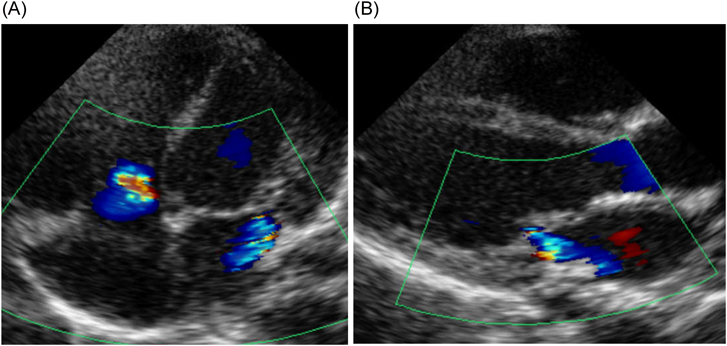

胎児心臓超音波検査ではCTAR47%,心横径ϕ35.6 mm,心拍数148 bpm,四腔は著明に拡大,右室壁の肥大を認め,僧帽弁輪径11.2 mm, MR重度,三尖弁輪径10.4 mm, TR重度,左室駆出率(Left ventricular ejection fraction; LVEF)50%であった(Fig. 1).肺動脈弁の狭窄はなく,動脈管,卵円孔の閉鎖は認めなかった.また,供血児はCTAR29%,心横径28.0 mmと週数相当であり房室弁逆流を認めなかった.在胎週数が早く,FLP後のため房室弁逆流が改善する可能性に期待し経過観察とした.分娩時期に関しては,供血児に異常がないため供血児を優先して判断する方針とした.経過中,胎児のnon-stress test(NST)では両児ともにreassuring patternで,臍帯血流の途絶が見られず観察を続けることができた.出生前の弁輪径とCTARの推移は在胎28週1日,僧帽弁輪径12.4 mm,三尖弁輪径14.1 mm.在胎29週5日,僧帽弁輪径12.9 mm,三尖弁輪径13.3 mmで在胎32週1日,僧帽弁輪径12.3 mm,三尖弁輪径13.6 mm, CTAR47%であり,重度のMR, TRは持続した.在胎32週4日,前期破水のため帝王切開とした.

Fig. 1 Fetal echocardiogram of the recipient at 27 weeks’ gestational age

(A) shows left and right atrial enlargement. (B) shows severe mitral and tricuspid regurgitation.